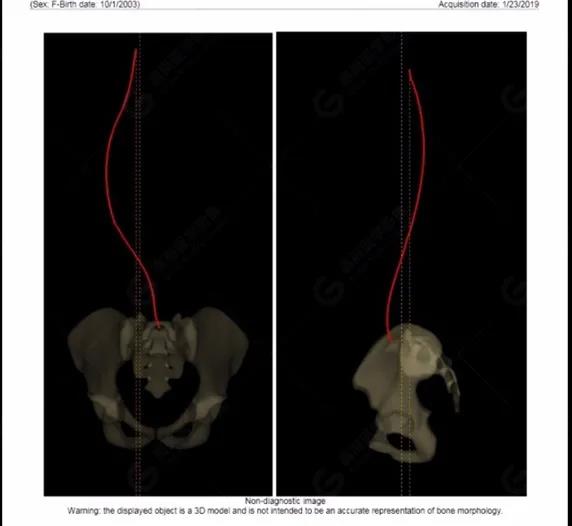

15歲女性,發(fā)現(xiàn)特發(fā)性脊柱側(cè)彎3年,于2019年1月23日來到廣東高尚醫(yī)學(xué)影像診斷中心行EOS檢查,2019年2月行手術(shù)治療后多次到中心行EOS復(fù)查。

2019-01-23

拍攝完畢后利用系統(tǒng)自帶的 Ster EOS 3D工作站對圖像進(jìn)行后處理,自動生成臨床常用的參數(shù)值以及DICOM圖像,如圖所示:(2019-01-23)

脊柱側(cè)彎最重要一個臨床參數(shù)是側(cè)彎角(Cobb角),目前臨床公認(rèn)的Cobb角>10 °診斷為脊柱側(cè)彎;如Cobb角進(jìn)行性持續(xù)性增加>40 °需要手術(shù)矯正治療。

本例患者胸椎右側(cè)彎,Cobb角(T6/T12)為47°,遂行手術(shù)矯正治療。術(shù)后多次隨訪的Cobb角(T10/L3)為12°-15°之間,較術(shù)前明顯縮小。